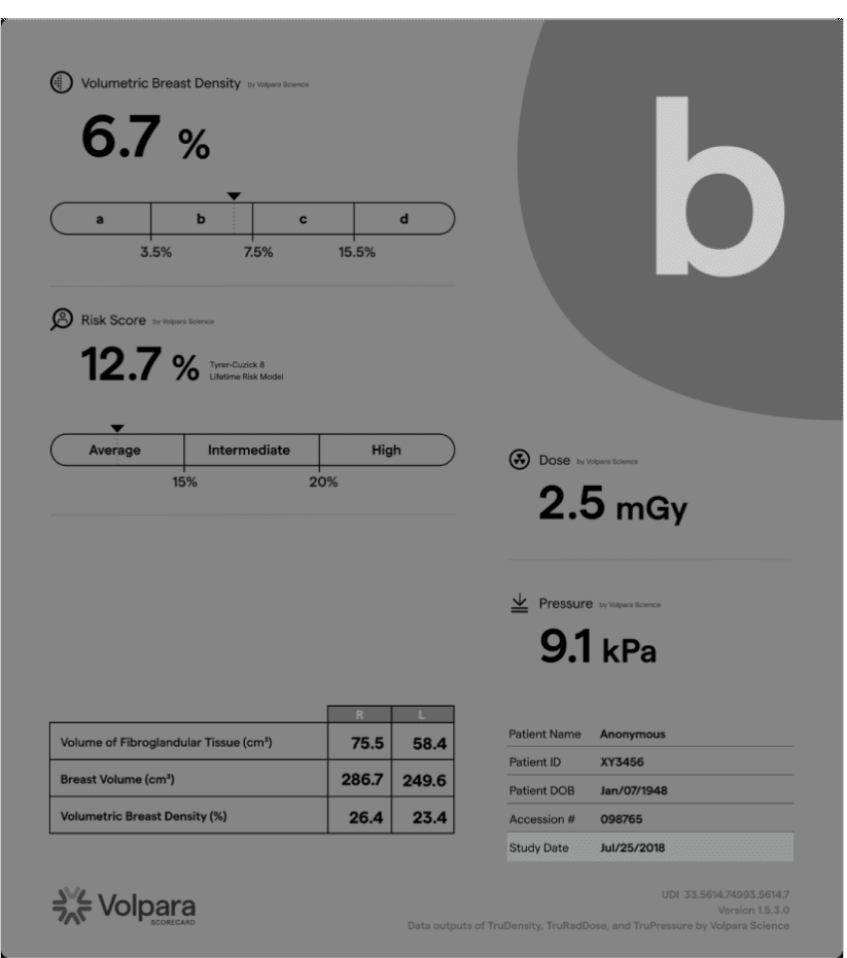

Volpara’s FDA-cleared TruDensity™ algorithm powers Scorecard, a breast density assessment software that delivers consistent, volumetric insights. It provides clinicians with consistent, objective data to support earlier cancer detection and supplemental imaging recommendations.

As the only breast density assessment software validated for use with Tyrer-Cuzick v8 (TC8), it provides precise data to support lifetime breast cancer risk assessment to help identify patients who may need additional imaging or preventive measures.

By providing an objective density score, we help clinicians determine when supplemental screening methods may be necessary, ensuring that high-risk patients receive the right care at the right time.